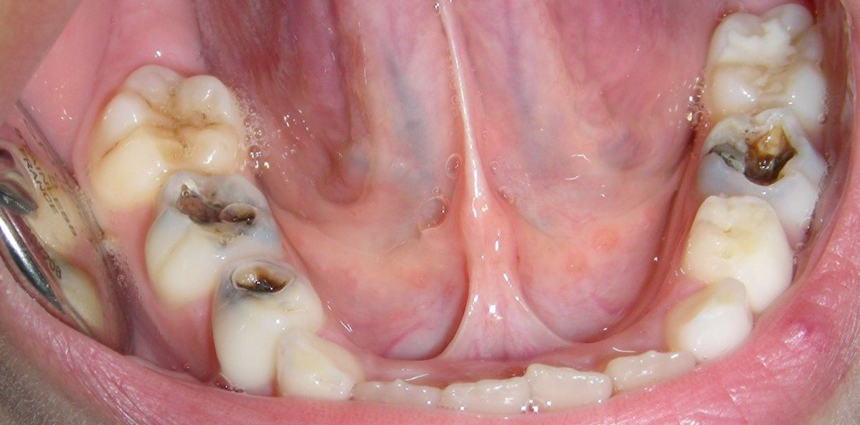

Bacterial infection

Bacteria can get into the pulp of a tooth through small openings created by tooth decay or injury. Inflammation or a bacterial infection of the pulp is the most common reason people see an endodontist.